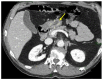

Gastritis cystica profunda (GCP) has been defined as a rare submucosal benign gastric lesion with cystic gland growth. Due to its unclear etiopathogenesis, this lesion is often misdiagnosed and mistaken for other gastric masses. Currently, a standardized treatment for GCP lesions is still missing. Here, we illustrate a case of a patient admitted to our general surgery department for melena and general discomfort. No history of peptic ulcer or gastric surgery was present. Upper GI endoscopy was performed, showing a distal gastric lesion with a small ulceration on the top. CT-scan and endoscopic ultrasound confirmed the presence of the lesion, compatible with a gastric stromal tumor, without showing any eventual metastasis. Surgical gastric resection was performed. Histological findings were diagnostic for GCP, with cistically ectasic submucosal glands, chronic inflammation, eosinophilic infiltration and foveal hyperplasia. GCP is a very exceptional cause of upper-GI bleeding with specific histological features. Its diagnosis as well as its therapy are challenging, resulting in several pitfalls. Even though it is a rare entity, GCP should always be considered in the differential diagnosis of gastric submucosal lesions.